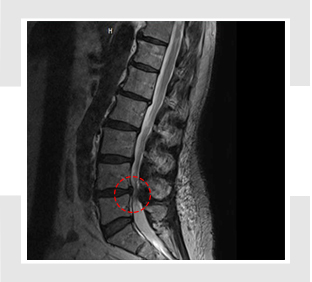

척추관 협착증 치료 방법

척추관 협착증 환자는 협착된 척추관 부근에 염증이 발생하여 심각한 통증을 느끼게 되고, 두꺼워진 인대가 신경을 압박하게 되고요. 자생한방병원에서는 염증과 부기를 가라앉히는데 효과가 있는 디스크 치료 한약으로 협착으로 인해 유발된 통증을 감량시켜주며, 부서진 근처 연조직의 흠집를 낫게 하죠. 한약은 퇴행된 뼈의 재생을 증대시키고 두꺼워진 인대 근처의 염증을 가라앉히는 효과가 있어요. 자생에서는 이런 한약과 나란히 척추관을 벌려주는 추나요법 등을 같이 진행하여 척추관 협착증을 치료하죠.

척추관 협착증이 진행하여 척수 손상의 증상이 나타나게 되면 다리의 경미한 운동마비, 건 반사 항진, 바빈스키 징조 등을 보이죠. 또한 감각장애로 통각, 운동감각 장애, 위치 진동감각 장애가 나타난다고 하고 신경인성 방광에 의한 배뇨 장애도 발생할 수 있어요. 수술 후, 통증 등은 호전을 보일 수 있겠지만 마비 등 일부 증상은 남을 수도 있어요.